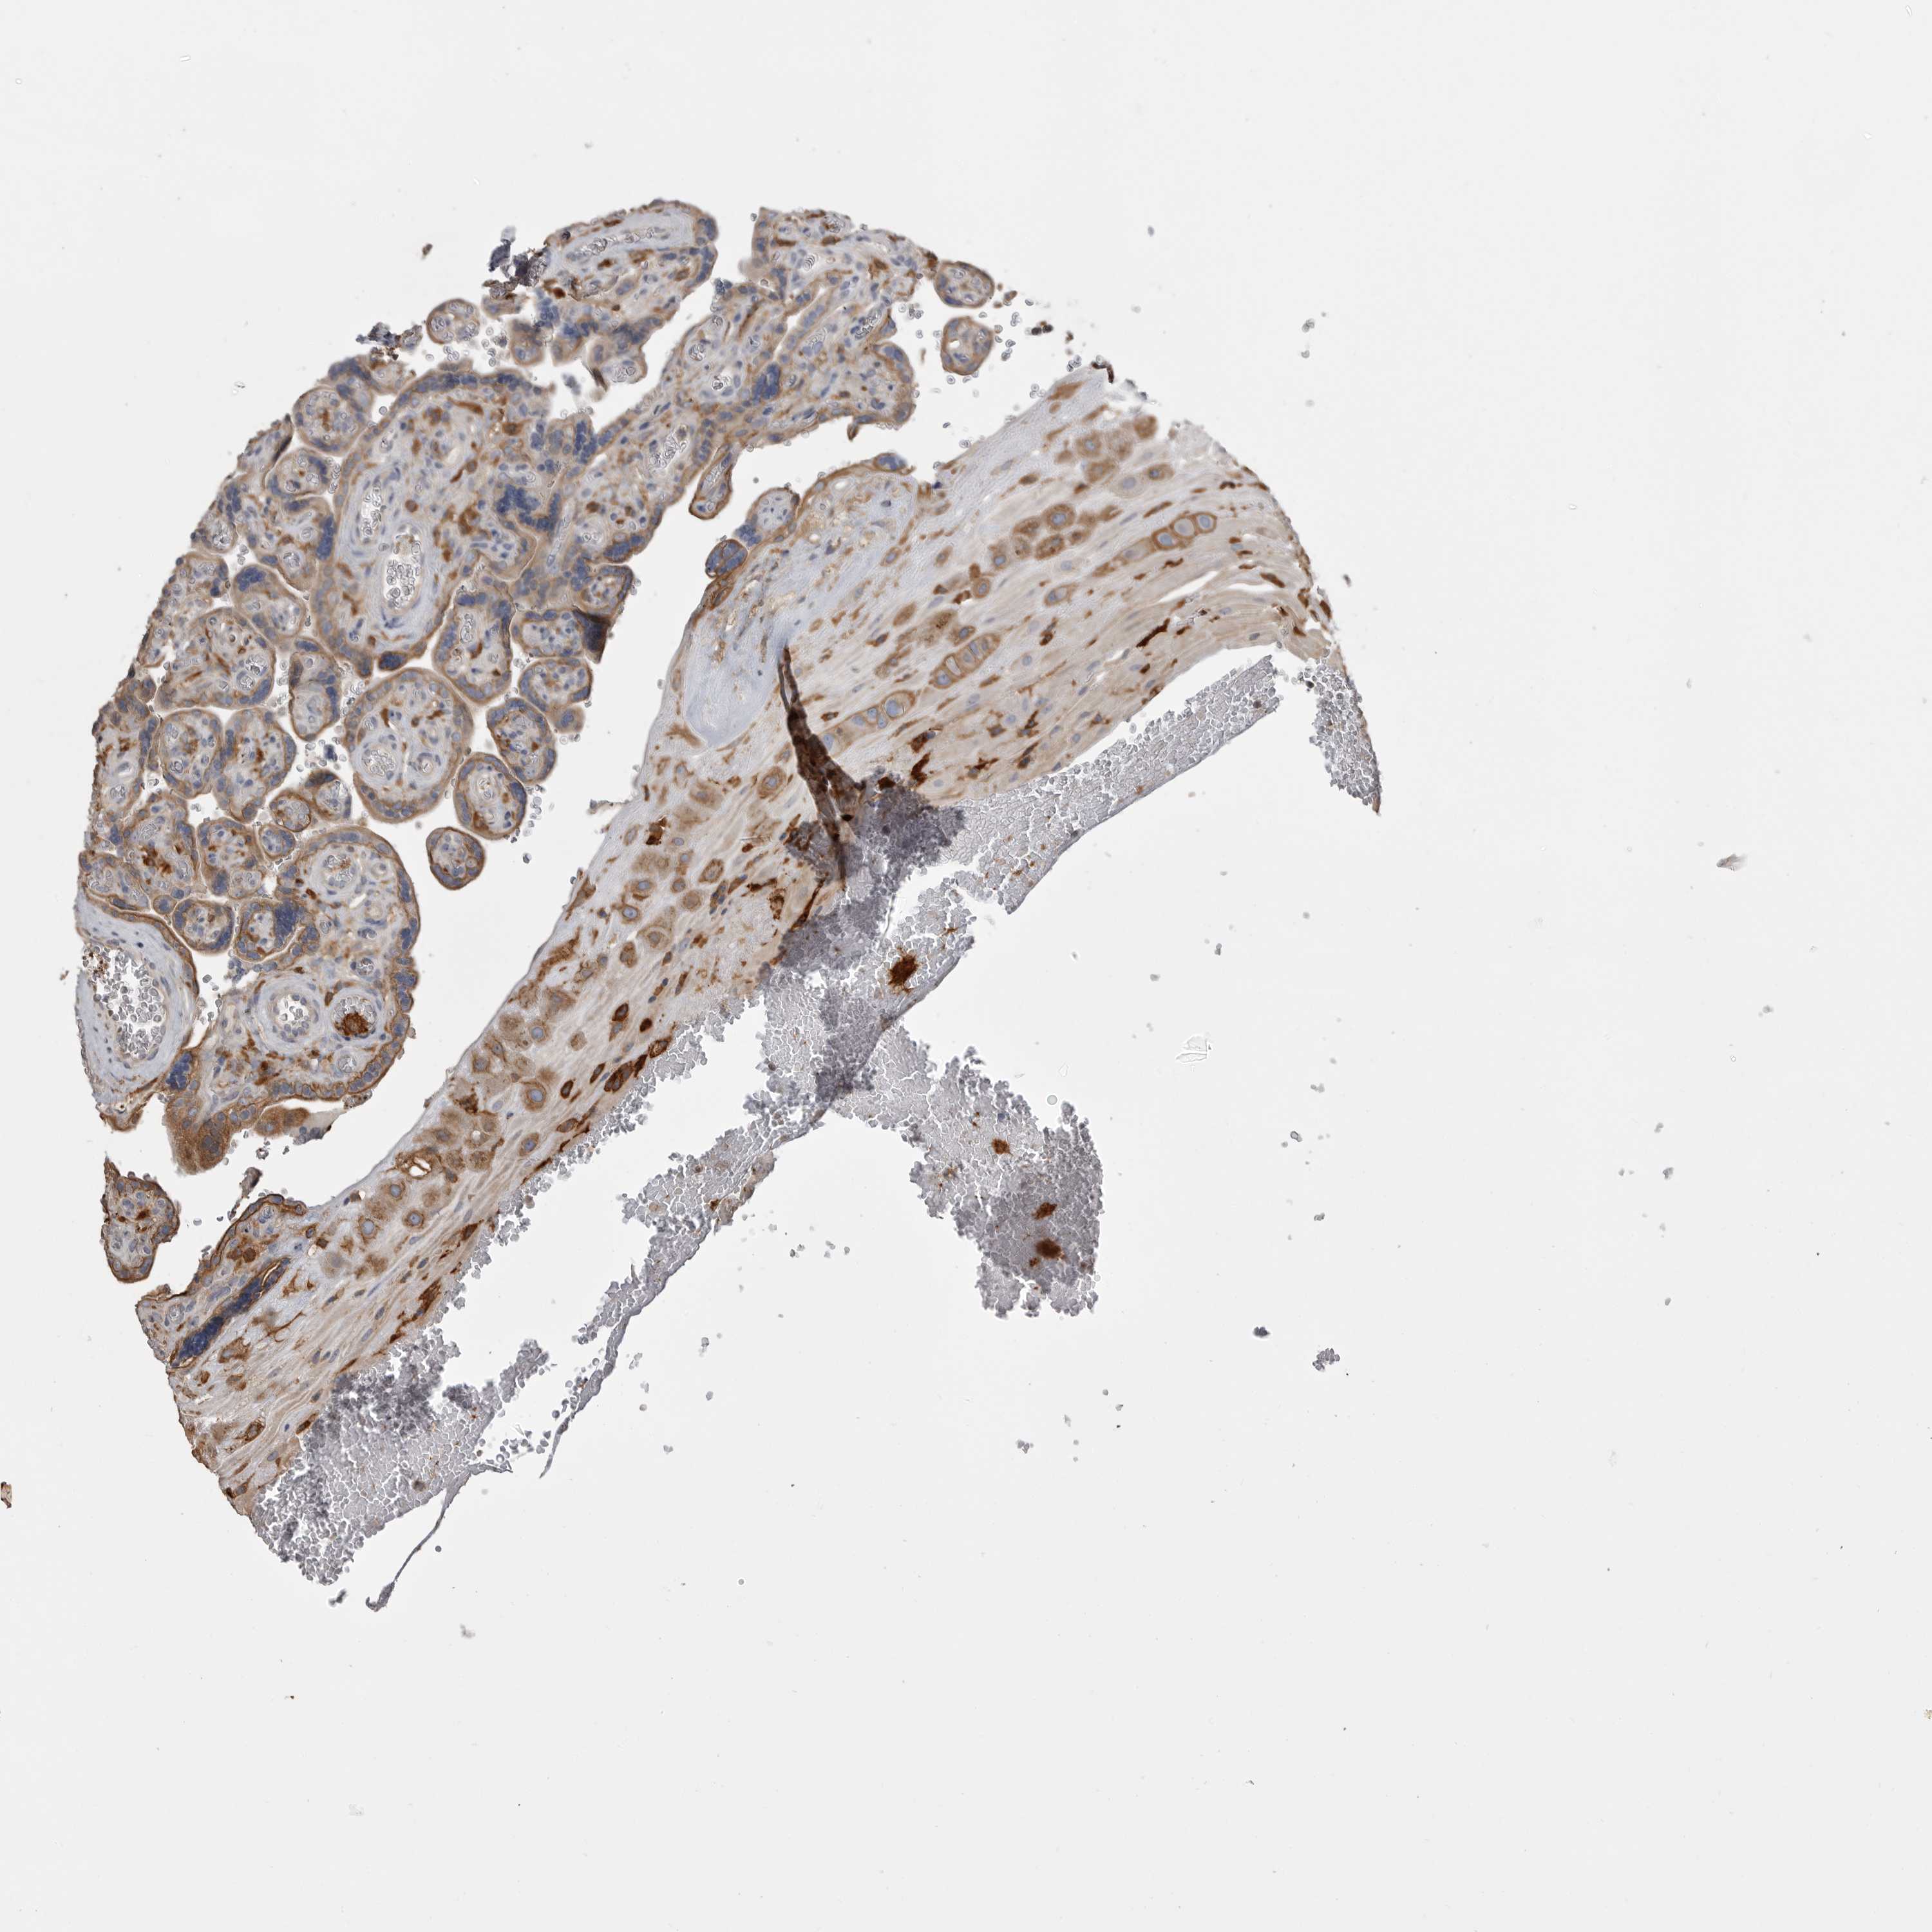

PLACENTA - Antibody stainingi

Antibody staining in the annotated cell types in the current human tissue is reported as not detected, low, medium, or high, based on conventional immunohistochemistry profiling in selected tissues. This score is based on the combination of the staining intensity and fraction of stained cells. Each image is clickable and will lead to virtual microscopy that enables deeper exploration of all samples and also displays staining intensity scores, fraction scores and subcellular localization as well as patient and tissue information for each sample.

Antibody HPA026980

Decidual cells Medium

Trophoblastic cells Medium